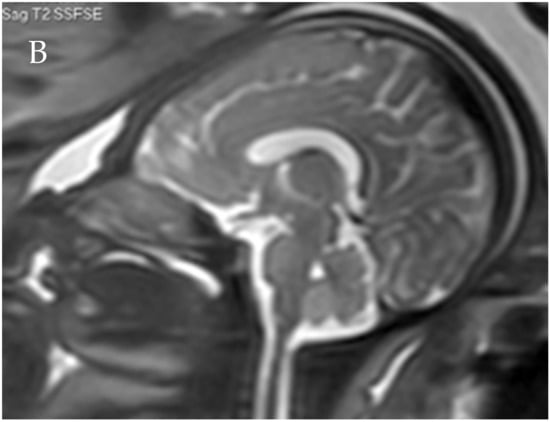

Figure 2.

Corpus callosum as captured by trans-abdominal mid-sagittal US scan at 23 weeks of gestation (A) and by mid-sagittal MRI scan at 33 weeks of gestation (B).